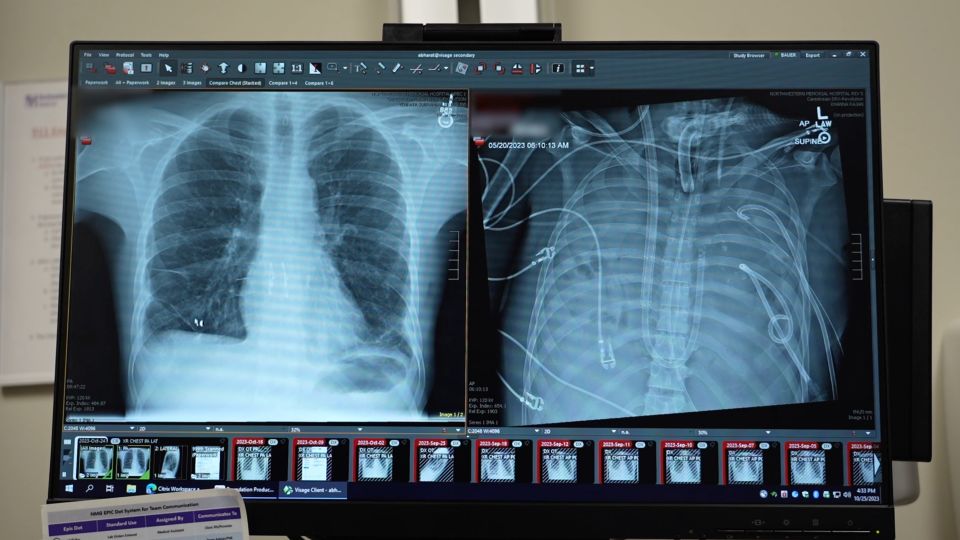

بدأت معاناة باور مع التنفس في نيسان، حين شعر بصعوبة العملية، مما أدّى إلى دخوله المستشفى. وعندما فشلت المضادات الحيوية في علاج عدوى رئته، اضطر الأطباء إلى استخدام جهاز ECMO لأكسجة دمه خارج جسده.

تضمنت هذه الاستراتيجية إزالة رئتي باور المصابتين واستخدام قنوات صناعية لتأمين دوران الدم في جسده، ووضع مستشعرات على الصدر لتثبيت قلبه موقتًا. كانت العملية معقّدة، لكنها نجحت، وتلقى باور رئتي مانح.

وفي التفاصيل، عندما فتح الأطباء صدر المريض تفاجأوا بوجود القيح، فعمدوا إلى إزالة الرئتين بعناية، حتى لا تنتشر أيّ جراثيم، وقاموا بتنظيف كلّ شيء ظنّوا أنه يحتوي على العدوى. في المقابل، أبقوا باور على المضادات الحيوية الثقيلة.

استغرقت العملية برمّتها بضعة أيام فقط. أزال الأطباء رئتي باور في 26 أيار، وأصبح زوج المانحين متاحًا في اليوم التالي. في 28 أيام، قام الجراحون بإزالة غرسات الثدي، وقاموا بإدخال رئتي المتبرّع.